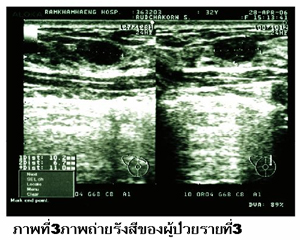

รายที่ 3

หญิงไทยโสดอายุ 25 ปี คลำพบก้อนที่เต้านมขวามานาน 1 เดือน. การตรวจภาพถ่ายทางรังสีปรากฏดังภาพที่ 3.

1. Ultrasonogram ของเต้านมข้างขวา.

2. เงาก้อนทึบก้องเสียงต่ำ ขอบเขตชัดเจนบริเวณ 2 นาฬิกาของเต้านมข้างขวาขอบเรียบขนาด 10x6x10 มม.

3. การวินิจฉัยโรคคือ fibroadenoma.